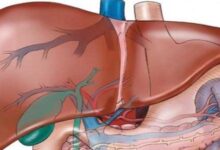

تعني دهون الكبد بأنّ هناك زيادةً في كمية الدهون المتراكمة في تجاويف الكبد ممّا يٌعيق عملها ويبطئه، الأمر الذي يؤشر إلى حالةٍ مرضيةٍ خطيرةٍ على صحة الإنسان تبدأ بتليّف الكبد وتنتهي بتشمّع الكبد، وقد يتطور المرض إلى التسبب بإصابة الكبد بالسرطان، كما تتسبب هذه الدهون بارتفاعٍ في نسبة الأنزيمات التي يفرزها الكبد مما ينتج عنها ارتفاع في مستوى الحديد في الدم.

تختلف مضاعفات تراكم الدهون في الكبد من شخصٍ إلى آخر؛ فالبعض تنتج لديه التهاباتٌ في الكبد تؤدي إلى توّقف عمل الكبد بالتدريج حتى تفقد قدرتها على العمل، فيفقد الجسم عضواً مهماً فيه، والبعض الآخر ينتج عنده تشمّعٌ وتليّفٌ في الكبد يتوقف عمله أيضاً، مما يتسبب بالوفاة.